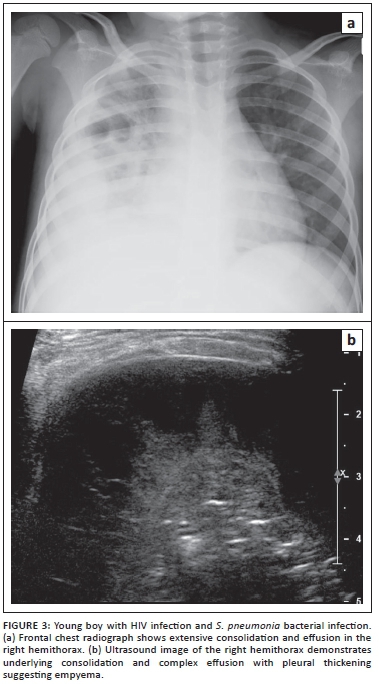

Outside of infancy, Streptococcus pneumoniae is the most common cause of bacterial infection and may be recurrent in pediatric patients with HIV infection. Other frequent pathogens include Hemophilus influenzae, Staphlococcus aureus (including methicillin resistant strains), Klebsiella pneumoniae, Salmonella spp. and Eschericia coli.5,6 Factors complicating treatment of bacterial infection include reduced efficacy of vaccines and reduced antibiotic susceptibility in children infected with HIV.7,8

Imaging findings of bacterial lung infections from S. pneumonia and S. aureus are similar in both children infected with HIV and immunocompetent children. They are characterised by diffuse patchy airspace disease in bronchopneumonia and confluent airspace disease with air-bronochograms in lobar pneumonia. However, these bacterial lung infections are often more severe in children infected with HIV and result in complications such as lung abscess and empyema (Figure 3).5,15